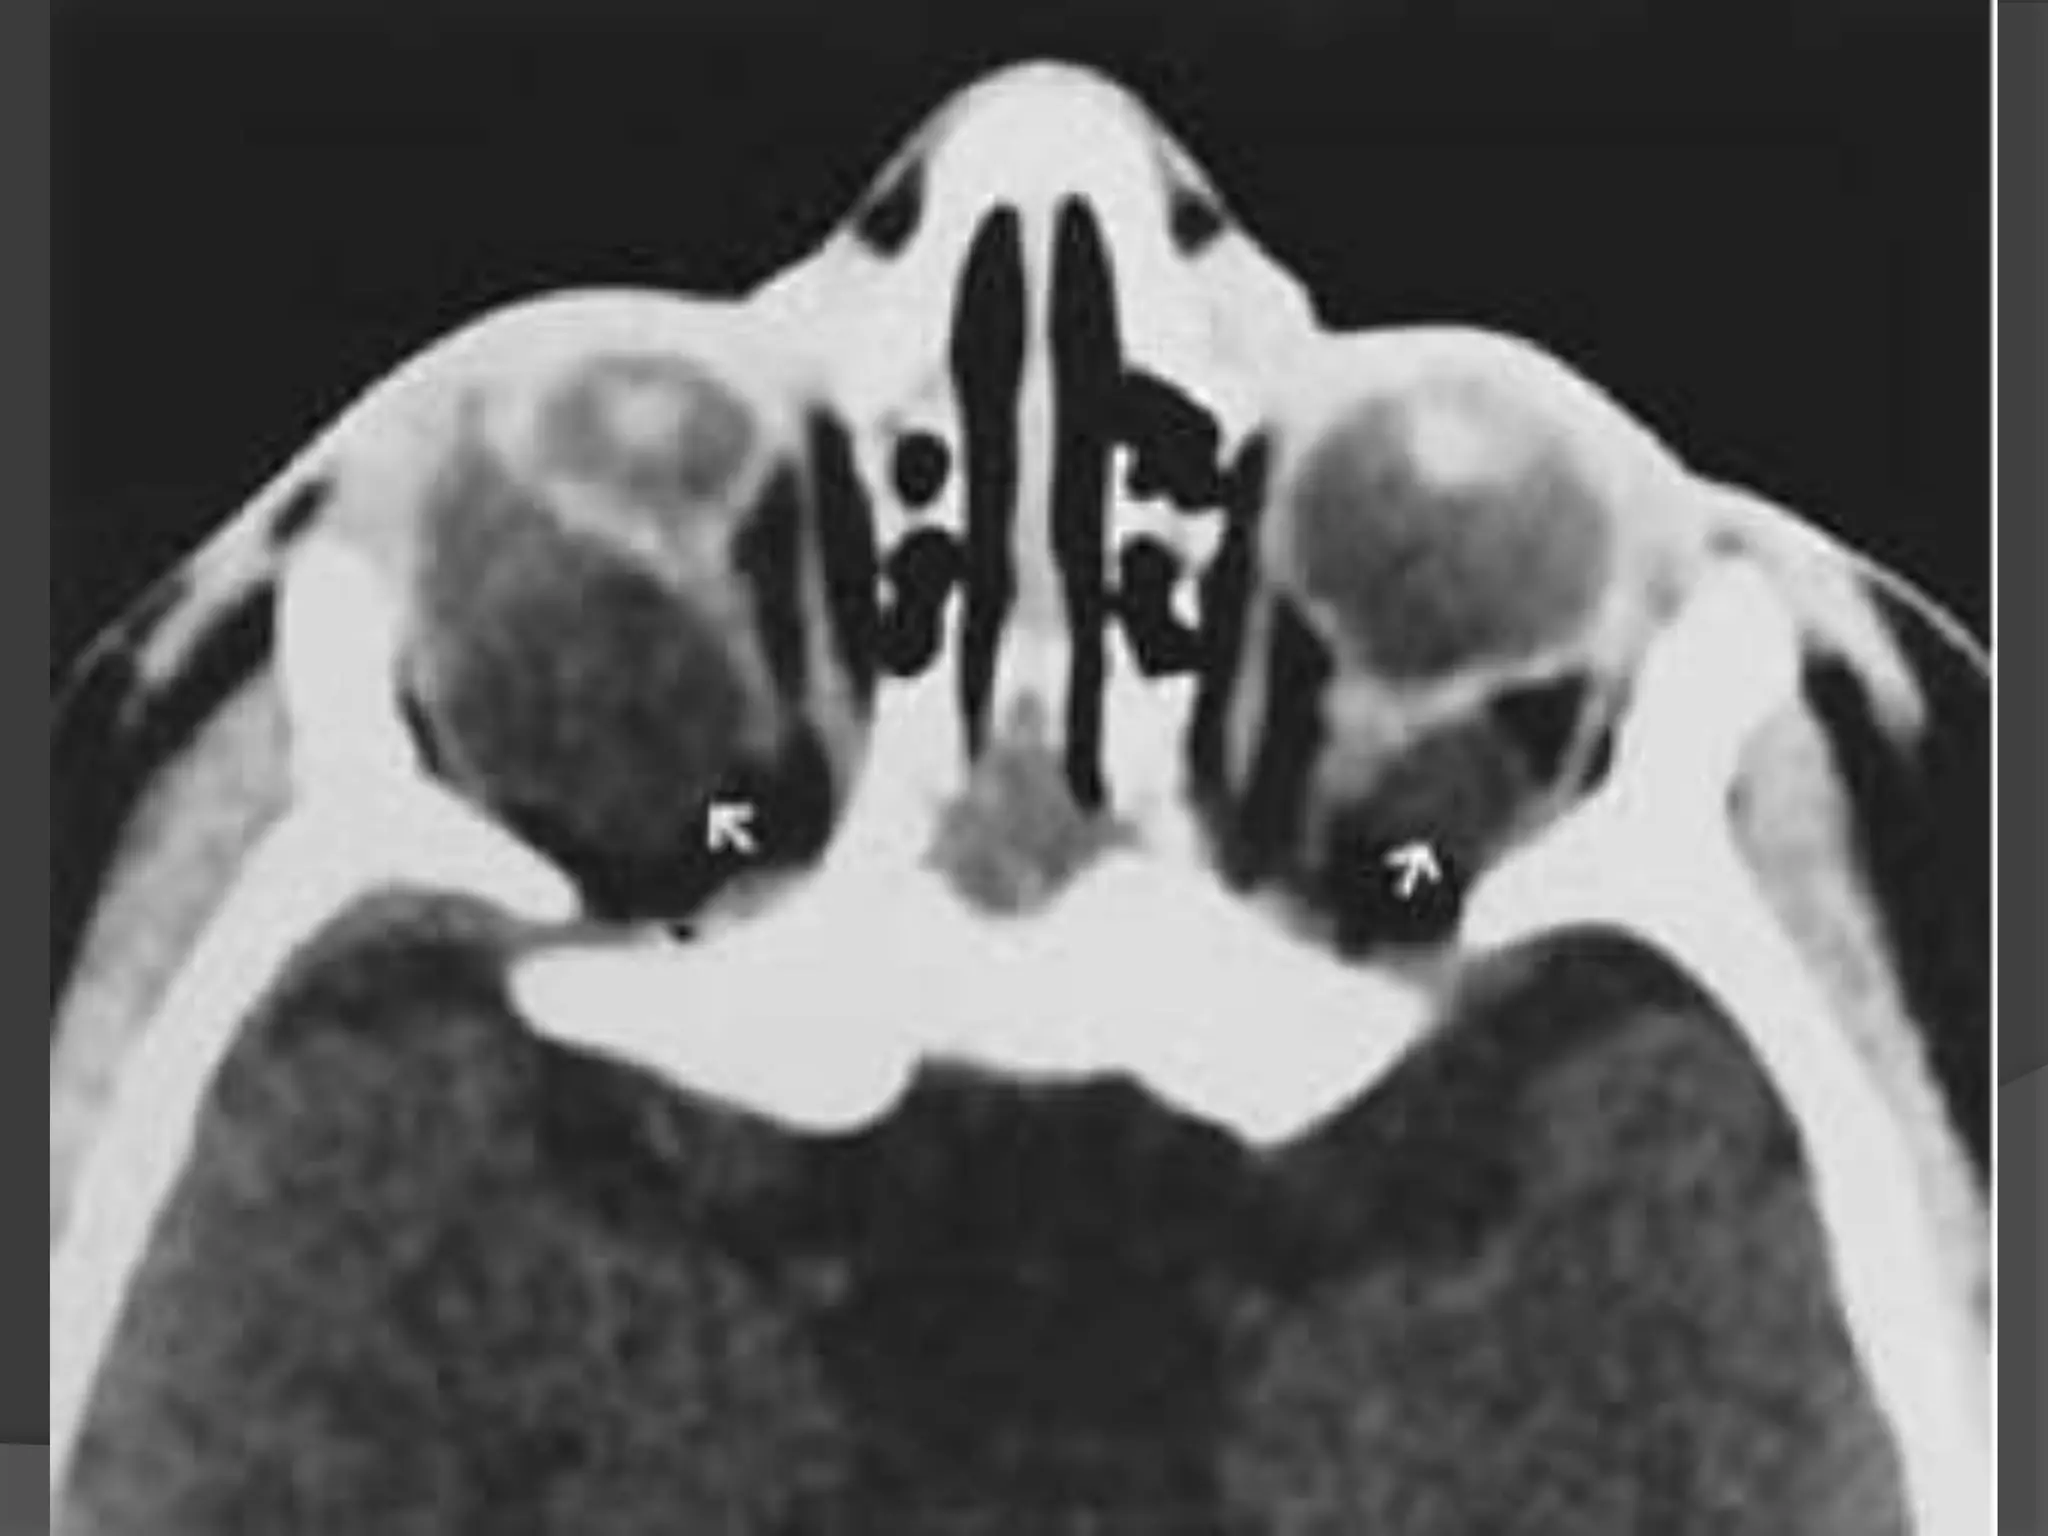

• #21 Granulomatous uveitis. A, Axial T2WI shows hypointense lesions (arrows). B, Axial enhanced, T1WI shows marked enhancement of the entire uveal tract (arrow). C, Unenhanced axial T1-WI shows nodular thickening of the posterior aspect of the right globe (arrow) and thickening of the anterior segment (arrowheads) of the right globe. D, Enhanced axial fat-suppressed, T1WI shows nodular enhancement of the posterior aspect of the right globe (arrowhead and open arrow) related to granulomatous involvement of the choroids.

• #22 Granulomatous uveitis. E, Enhanced sagittal T1WI shows granuloma at the optic disc (white arrowhead) as well as involvement of the optic nerve (black arrowhead ). F, Enhanced axial fat-suppressed, T1WI shows enhancement of the markedly thickened uveal tract (arrowheads).